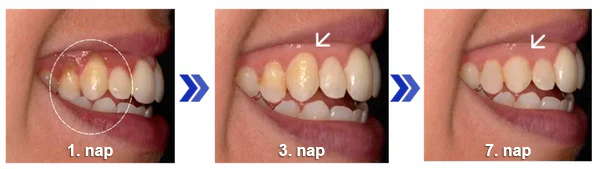

1.nap – Kezdjük!

Azonnali enyhülés a fájdalomra és a gyulladásra, a fogíny elkezd nyugodni.

A hatékony összetevők gyulladáscsökkentő hatásúak és elindítják a gyógyulási folyamatot.

Használd a port naponta az utasítások szerint.

3. nap – Látható gyógyulás

Valószínűleg jelentős csökkenést fogsz észrevenni a pirosságban, duzzanatban és vérzésben.

Sok ügyfél számol be róla, hogy már csak 7 nap után látható és érezhető javulást tapasztal, miközben az erőteljes regeneráló összetevők kifejtik hatásukat.

A kitartás a siker titka a tartós fogínyregenerációhoz.

5. nap – Visszaállított erő

A fogíny erősebbnek és egészségesebbnek fog tűnni, nagyobb ellenálló képességgel.

A formula aktívan elősegíti a kollagénszintézist, erősítve a fogíny szöveteit.

8. nap – Megújult önbizalom

Éld át a fogíny szövetének jelentős regenerációját és a fogszerkezet megerősödését.

Visszakapod az önbizalmad, mosolyoghatsz, ehetsz és szociális életet élhetsz szégyenérzet nélkül.